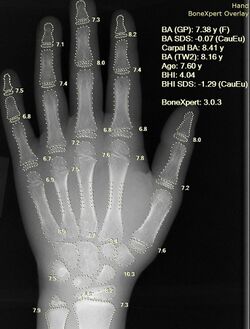

X-ray of a hand, with automatic calculation of bone age by a computer software

AI in healthcare is often used for classification, to evaluate a CT scan or electrocardiogram or to identify high-risk patients for population health. AI is helping with the high-cost problem of dosing. One study suggested that AI could save $16 billion. In 2016, a study reported that an AI-derived formula derived the proper dose of immunosuppressant drugs to give to transplant patients.[82]